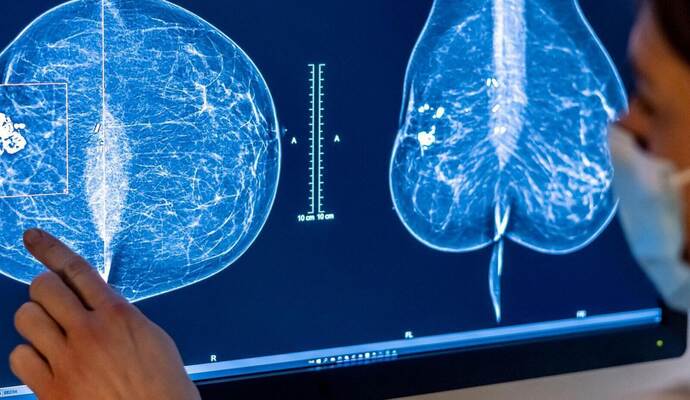

Monika Bühler-Wagner ist es wichtig, darauf hinzuweisen, dass bei den beiden häufigsten Erkrankungen (Brust- beziehungsweise Prostatakrebs) 90 Prozent der Betroffenen überleben. Generell spiele Künstliche Intelligenz bereits in vielerlei Hinsicht eine Rolle. Grundsätzlich seien Differenzierung in der Behandlung und eine gezieltere Medikamentengabe positive Faktoren. Nach den Erfahrungen von Monika Bühler-Wagner ist allerdings ein Nebeneffekt dieses Aspekts eine Verunsicherung der Betroffenen.